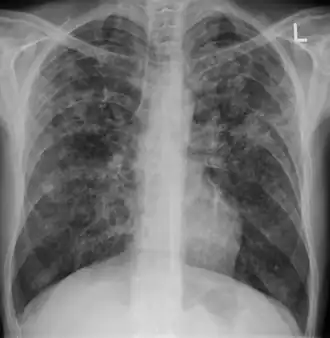

Miliary tuberculosis is a form of tuberculosis that is characterized by a wide dissemination into the human body and by the tiny size of the lesions (1–5 mm). Its name comes from a distinctive pattern seen on a chest radiograph of many tiny spots distributed throughout the lung fields with the appearance similar to millet seeds—thus the term "miliary" tuberculosis. Miliary TB may infect any number of organs, including the lungs, liver, and spleen.[2]

A case of miliary tuberculosis in an 82-year-old woman:

-

X-ray, 13 days after onset, showing bilateral interstitial infiltrates -

X-ray, 22 days after onset, showing extensive bilateral reticulo-nodular infiltrates -